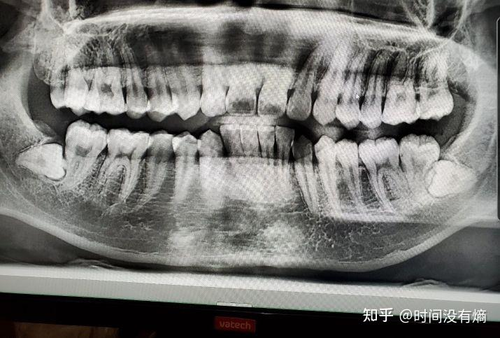

有的人长了智齿,可是智齿没有炎症,也不会影响到其他周围正常的牙齿,就没有去医院拔牙。然而有的人智齿就比较麻烦了,很容易发炎的,发炎的时候对于正常饮食也会有很大的影响。那么智齿拔牙后的注意事项有哪些呢?